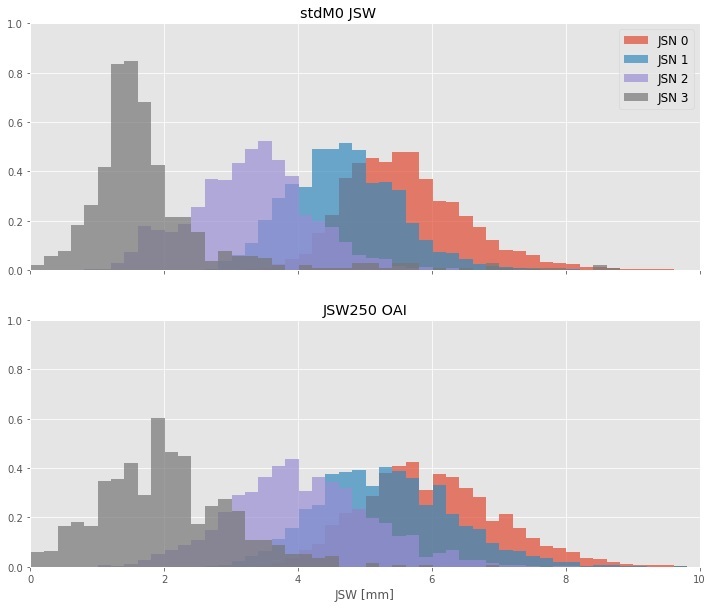

Joint Space Width (JSW) has been the gold standard to assess loss of cartilage in knee OA. Here we describe a novel quantitative measure of joint space width, standardized JSW (stdJSW). We assess the performance of this quantitative metric for joint space widthat tracking Joint Space Narrowing OARSI grade (JSN) changes and provide reference values for different joint space narrowing OARSI grades and their annual change.

We collected 18.934 individual knee images from the OAI study, from the follow-up visits up to month 48 (baseline plus 4 follow-up exams). Absolute JSW measurements and JSN readings were collected from the OAI study. Standardized JSW and 12-month changes were calculated for each knee. For each JSN grade and 12-month grade change, the distribution of JSW loss was calculated both for standardized JSW as well as absolute JSW measurements retrieved from the OAI study. Area under the curve of the ROC curves was calculated for the performance of both absolute and standardized JSW at discriminating between different JSN grades. Standardized response mean (SRM) was used to compare the responsiveness of the two measures to change in JSN grade.

Results

The areas under the ROC curve for stdJSW at discriminating between successive JSN grades were AUCstdJSW= 0.87, 0.95, and 0.96, for JSN>0, JSN>1 and JSN>2, respectively, whereas these were AUCfJSW= 0.79, 0.90, 0.98 for absolute JSW. We find that standardized JSW is significantly more responsive than absolute JSW, as measured by the Standardized Response Mean. Furthermore, we present reference values for standardized JSW stratified by base JSN grade and 12-month JSN change.

Our results show that standardized JSW is a better choice to track changes in JSN and to discriminate between JSN grades. Furthermore, our results show that standardized JSW cancels part of the normal variation in JSWs that comes from height variation.